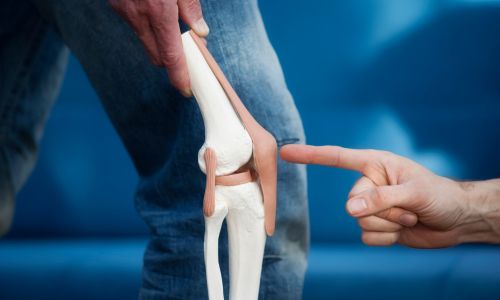

Joint Replacement

Total and partial replacement of knee, hip, and shoulder joints to restore mobility and relieve chronic pain.

Knee Arthroscopy

Targeted treatment for ACL issues, meniscus tears, and cartilage damage.